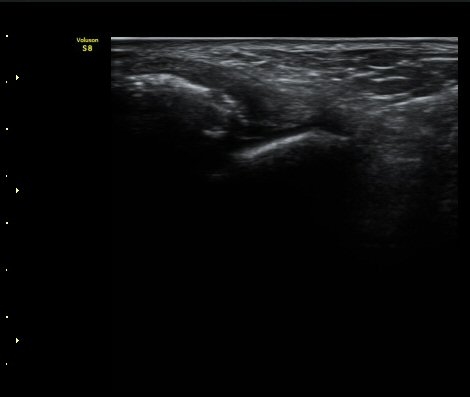

ÃÊÀ½ÆÄ Åõ½ÃÇÏ ºÎÇϰ˻翡¼­ ºñ°ñ°ú ÀδëºÎÂøºÎ¿Í  ºñ°ñ°ú °Å°ñ»çÀ̰¡ ¹ú¾îÁöÁö ¾Ê´Â´Ù

(樨毢 2).

±×¸²6) 3ÁÖ ÈÄ ÃßÀû°Ë»ç